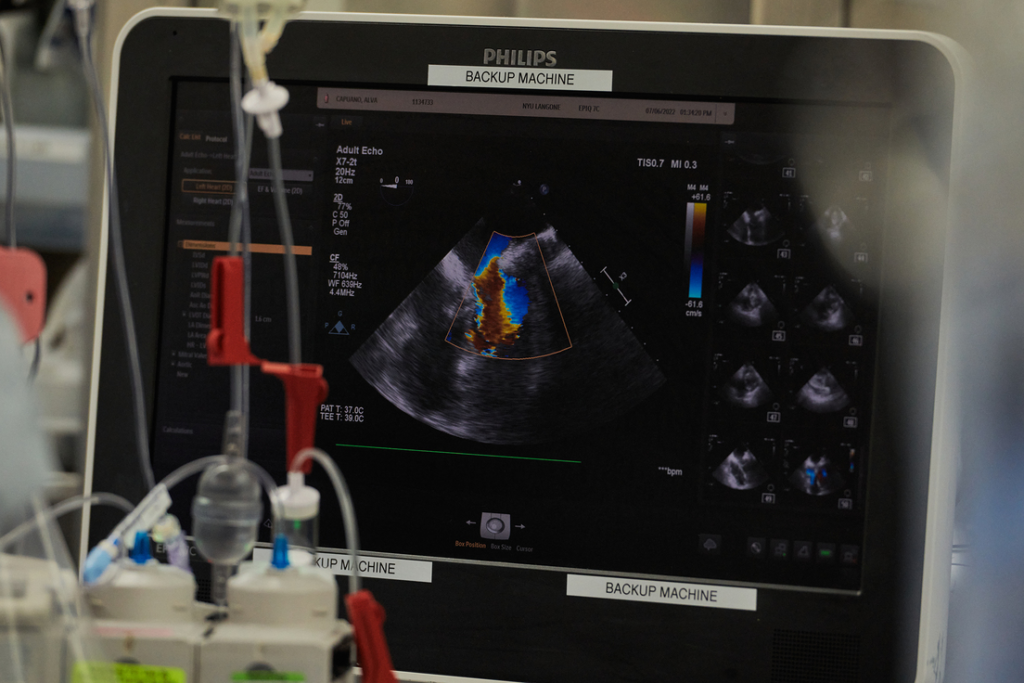

Cirujanos de la Universidad de Nueva York han trasplantado con éxito corazones de cerdo modificados genéticamente a dos pacientes con muerte cerebral, acercándose un paso más a la meta a largo plazo de usar partes de cerdo para abordar la escasez de órganos humanos para trasplante.

Según los investigadores que llevaron a cabo el procedimiento, los órganos funcionaron normalmente, sin signos de rechazo por parte del organismo, durante los experimentos de tres días en junio y julio. “Pudimos capturar en tiempo real todo lo que estaba pasando durante ese período de 72 horas”, afirmó Robert Montgomery, el director del Instituto de Trasplantes Langone de la universidad neoyorquina, en una conferencia de prensa este martes citado por Reuters.